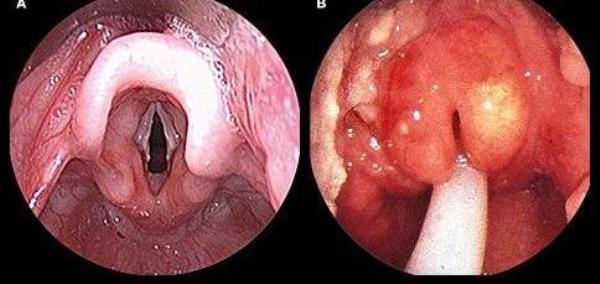

Диагноз эпиглоттита подтверждается при проведении ларингоскопии, фиброларингоскопии или фарингоскопии. Эти методы исследования позволяют выявить покраснение и увеличение надгортанника, а также отёк окружающих его тканей. Иногда возможно обнаружить гнойники.

Изображение показывает состояние горла при эпиглоттите

Инструментальный метод, который чаще всего используется для подтверждения диагноза эпиглоттита у детей, — фиброларингоскопия. Если такая возможность отсутствует, то проводится фарингоскопия, прямая или непрямая ларингоскопия. При остром эпиглоттите у детей эндоскопические признаки включают яркую гиперемию и увеличение размеров надгортанника, его малоподвижность, отек черпало-надгортанных складок и черпаловидных хрящей. При абсцедирующей форме эпиглоттита у детей в зоне наибольшей инфильтрации надгортанника можно обнаружить подслизисто расположенный гнойник.